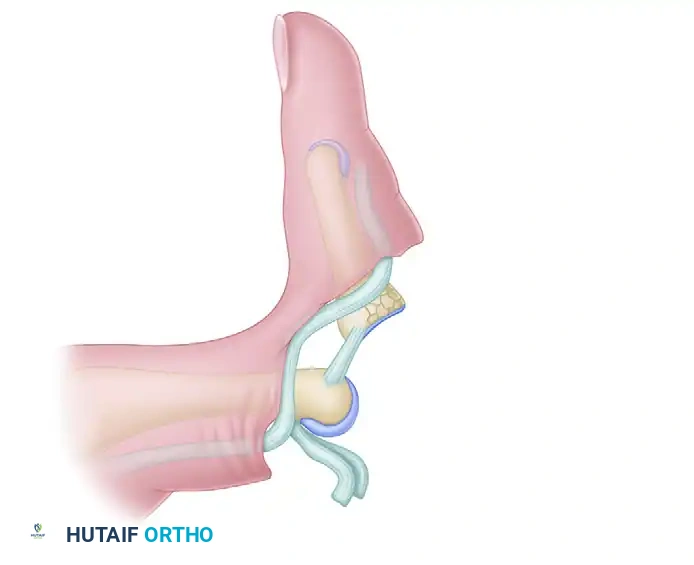

A PIP joint fracture-dislocation is a devastating injury that, as a rule, results in an unstable dorsal displacement of the middle phalanx. This pathoanatomy is caused by the disruption of the attachment of the volar fibrocartilaginous plate, often taking a fragment of the volar lip of the middle phalanx with it.

- Large Single Fragment (>50% Articular Surface): If a large, single volar fragment involving more than 50% of the joint surface is present, ORIF is indicated. Fixation can be achieved with one or more K-wires, minifragment screws, or a wire loop pullout technique.

A size-matched segment of the distal hamate articular surface is carefully shaped to match the comminuted contour of the middle phalanx. The distal hamate (articulating with the base of the 4th and 5th metacarpals) possesses a central ridge that perfectly mimics the median ridge of the middle phalangeal base, providing exceptional coronal plane stability.

Figure 67-49A: Persistent dorsal PIP joint subluxation with a nonreconstructible middle phalangeal volar lip fracture.

Step-by-Step Hemi-Hamate Surgical Technique

- Volar Approach: A volar Bruner or midlateral incision is made to approach the PIP joint. The flexor tendon sheath is opened, and the A3 pulley is released. The flexor tendons are retracted laterally.

- Joint Exposure ("Shotgunning"): The volar plate is released distally. The collateral ligaments are sharply released from their proximal attachments to allow the joint to be hyperextended or "shotgunned." This provides unparalleled visualization of the articular defect on the middle phalanx.